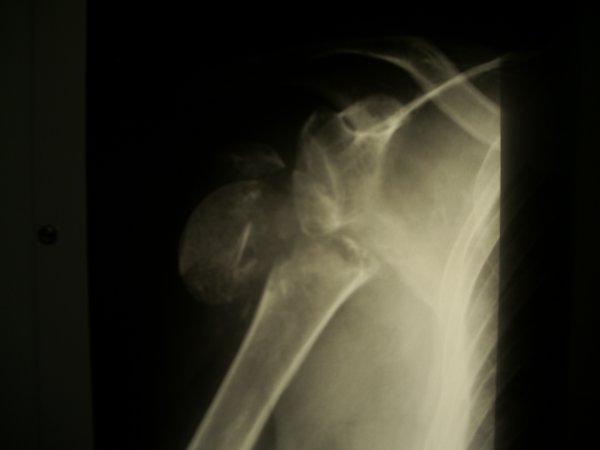

Lata po upadku na bark pojawila sie artroza.